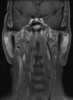

Enlarged lateral retropharyngeal lymph node